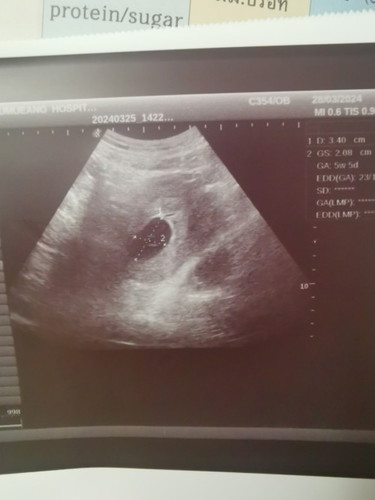

อายุครรภ์ตาม อัลตราซาวน์กับประจำเดือนต่างกันมาก

อายุครรภ์นับตามประจำเดือนคือ10 สัปดาห์ แต่ไปอัลตราซาวด์แล้วพบถุงการตั้งครรภ์ขนาด5สัปดาห์ ต่างกันมากเลยค่ะ ผิดปกติมั้ยคะ

ไม่ค่อยดีค่ะ ช่วงนี้คุณหมอน่าจะนัดอัลตร้าซาวบ่อยหน่อย (สัปดาห์ละครั้ง) เพื่อดูว่าหลังจากนี้น้องยังโตตามอายุที่อัลตราซาว์ได้ไหมค่ะ เราเคยนับอายุครรภ์ได้ 8 สัปดาห์ แต่ไปตรวจอัลตราซาวน้องเหมือน 5 สัปดาห์ สรุปครรภ์นั้นเราแท้งไป แต่ตอนนี้ตั้งครรภ์ใหม่แล้วค่ะ ครรภ์ใหม่น้องปกติดี เป็นกำลังใจให้คุณแม่ค่ะ

บ้านนี้ไปตอนอายุครรภ์7w พบตัวอ่อนเจอหัวใจกระพริบ ขนาดเท่า4-5w แอบกังวลเหมือนกันค่ะ😂

เหมือนกันคะ นับประจำเดือน10week แต่ถุงตั้งครรภ์ 7week ล่าสุดไม่เจอตัวน้องคะ